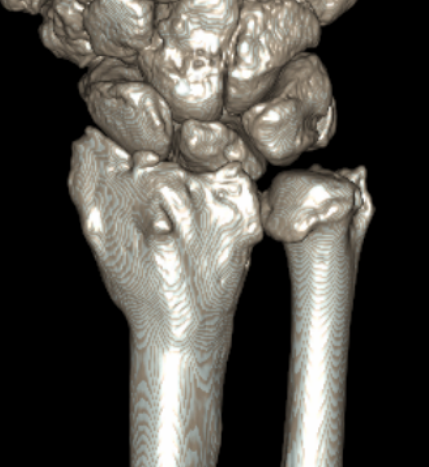

CT

CT guided 3D planning

- RCT of 40 patients with radial malunion

- 2D versus 3D planning and patient specific surgical guides

- 3 degree better correction in 3D group

- non significant trend towards better outcomes in 3D group